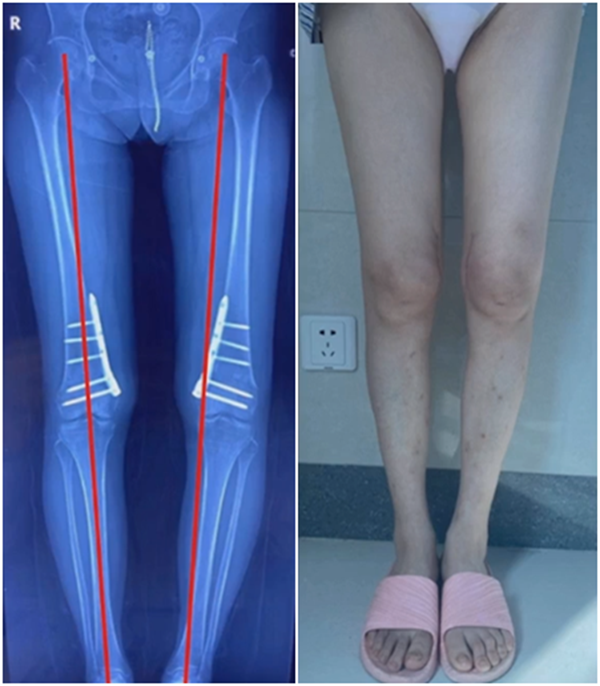

病例,X患者,女,双侧外翻膝,行双侧DFO。

术后6周摔伤,一侧出现膝内翻。

进行翻修,术前力线显示内翻。